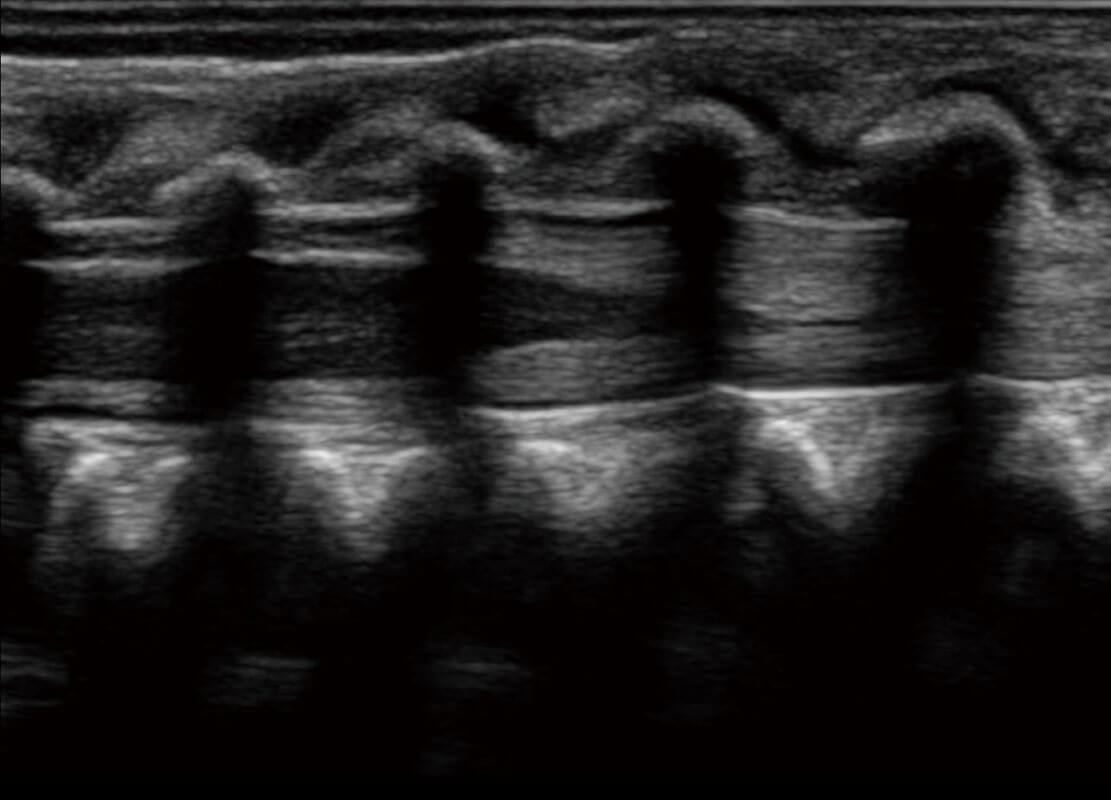

盆底超声

P60为盆底超声检查提供应用方案,多种腔内及腹部容积探头提供从二维、三维到四维的优异图像品质,实时快速三维容积数据获取,专业的测量工具包等人性化设计,为超声医生诊断提供有力保障。